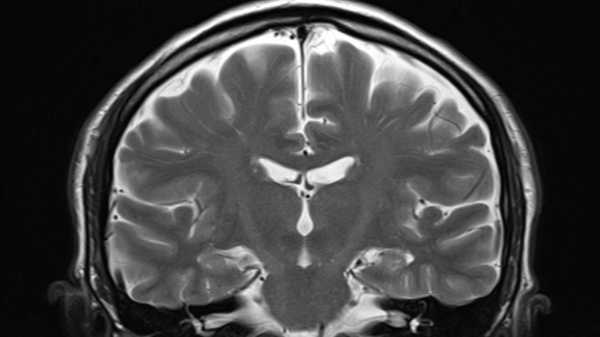

Сканування мозку може розкрити ваш справжній біологічний вік